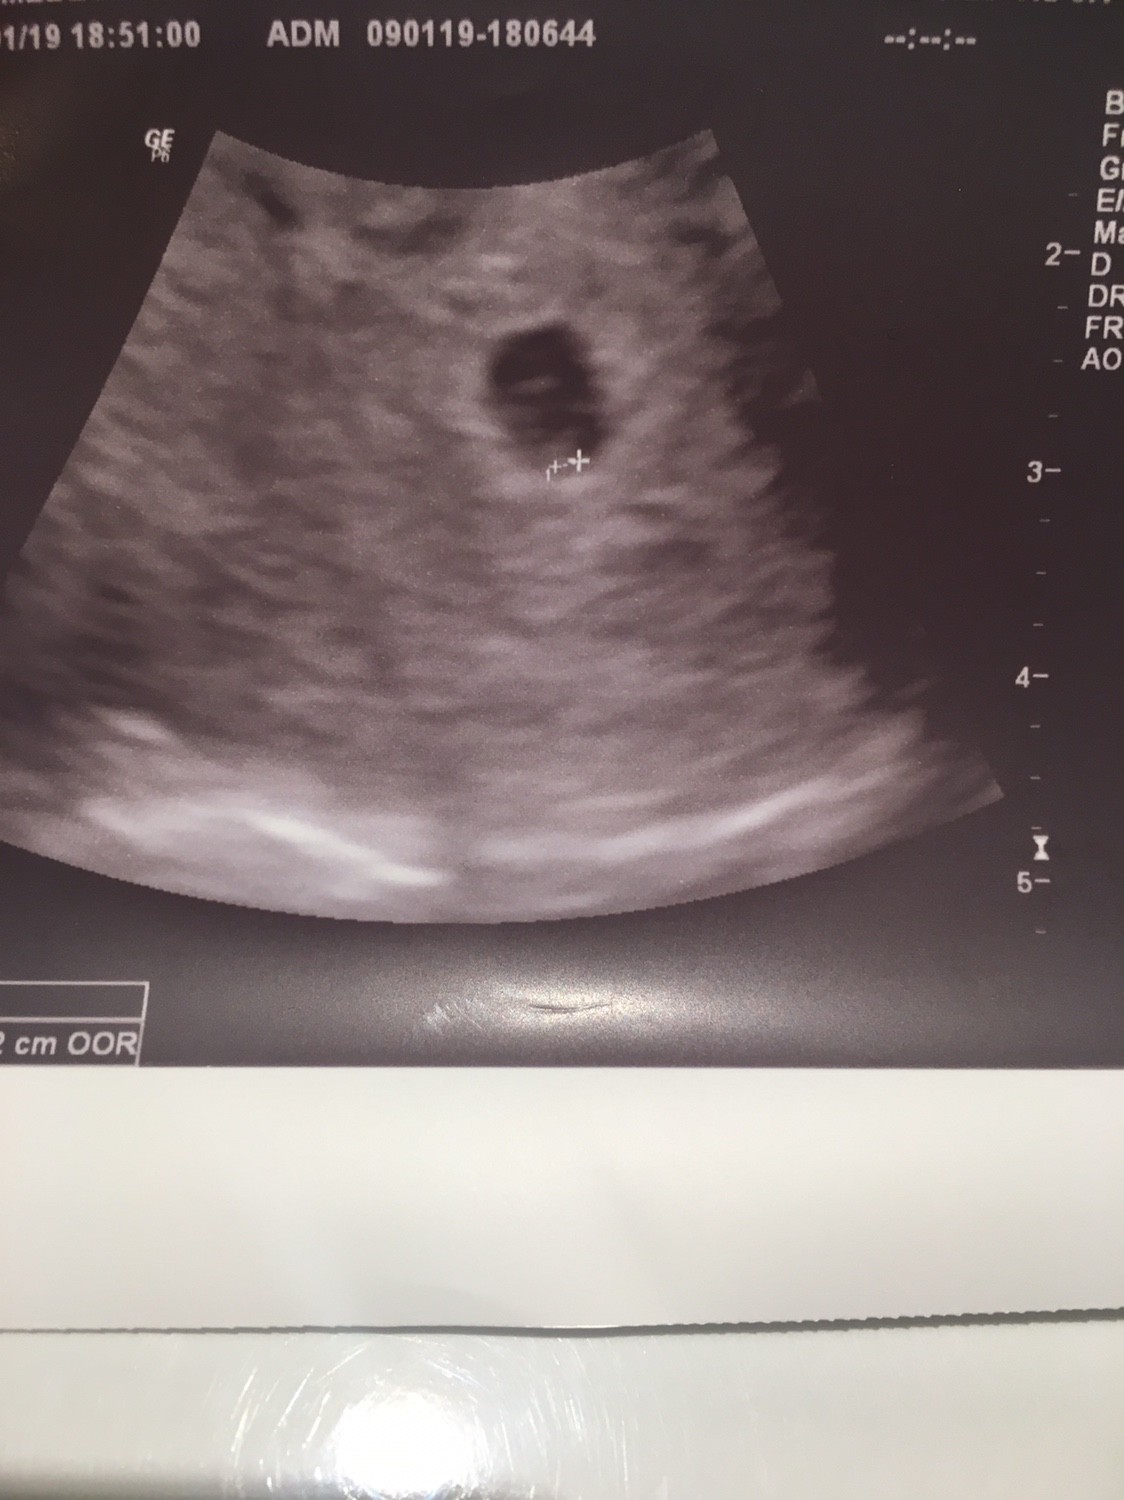

Hej dziewczynki, u mnie na dzisiejszym USG malutki pecherzyk. Lekarz do progeteron zapisał mi jeszcze acard 1x1dziennie i następna wizyta 23.01. jeszcze we wtorek muszę podskoczyć do położnej po L4.

Przedstawiam wam moja kropeczke :)

IMG_2222.JPG

Serduszka jeszcze nie zobaczyłam, ale lekarz mnie uspokoił, że zarodek jest jeszcze malutki bo 1,2 mm :D trochę się uspokoiłam. Dostałam zaświadczenie i L4 No i kolejna wizyta za 2 tygodnie :)